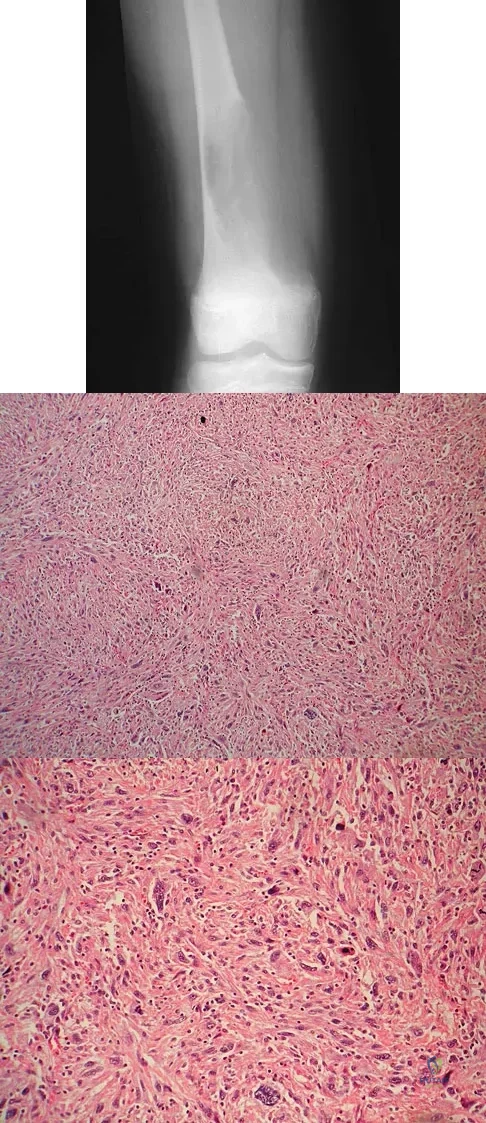

Question 18

Question 20